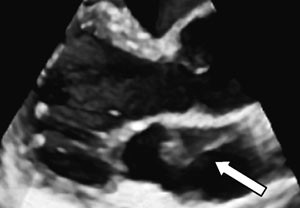

Transtorakal ekkokardiografi var ikke tilstrekkelig til å stille en sikker diagnose. Vi valgte derfor å gå videre med transøsofageal ekkokardiografi, som viste at membranen dekket en relativt stor del av atriet (fig 3). Det så ut til å være god passasje for blodstrømmen, siden det ikke var tegn til utvidelse av atriet proksimalt for membranen. Det var heller ikke andre tegn til obstruksjon, som tåkevirvler i den bakre del av atriet eller retrograd blodstrøm i lungevenene. Membranen var lokalisert basalt for aurikkelen. Det dreide seg dermed om en venstre atrie-membran.

Den transøsofageale undersøkelsen har betydelige fordeler fremfor den transtorakale når det gjelder strukturer i atriene, pga. av fysiske begrensninger ved ultralydteknologien. Hos denne pasienten kunne transøsofageal ekkokardiografi bekrefte diagnosen og belyse betydningen av membranen for blodstrømmen.